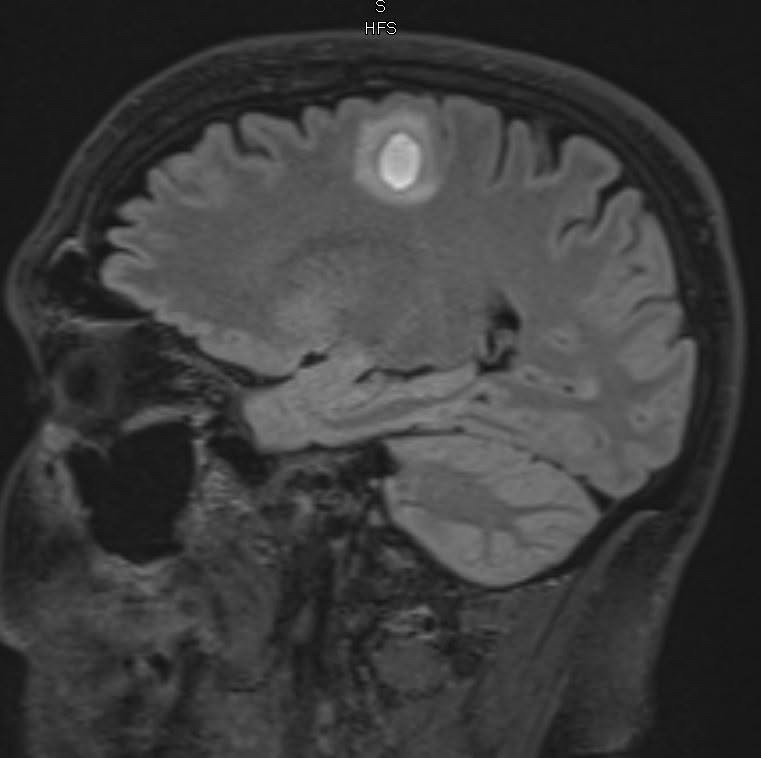

Four weeks ago, doctors discovered the cancer had spread to his brain. He now has three brain tumors. Two weeks ago, he began radiation treatment to try to slow/stop them.